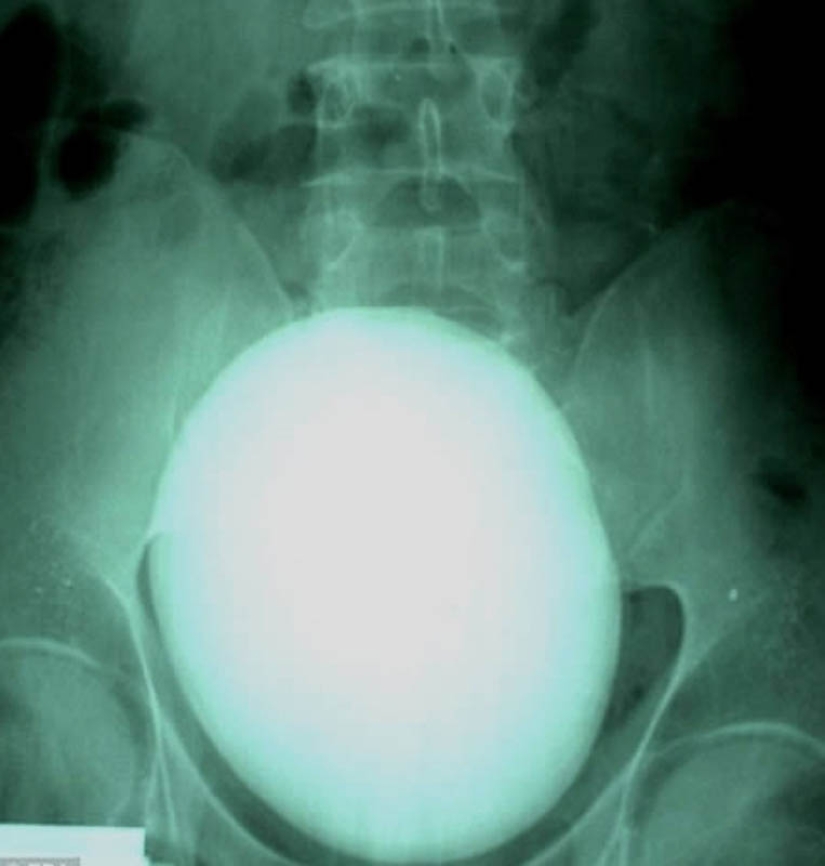

17. Un paciente de Hungría retiró un cálculo renal de 15 centímetros que pesaba 1,1 kilogramos.